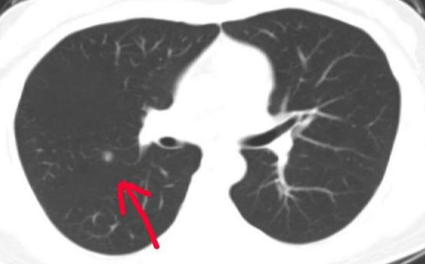

根据肺部结节直径的不同,大致可分为以下几种:微小结节是指直径小于5毫米的结节;小结节结节直径5-10毫米。以上两种肺结节病症类型,如无其他不适的症状或者危险因素,可以先定期随访观察。肺部结节是指直径为10-30毫米的肿块,这类结节应根据患者的具体病情采取相应的治疗措施。对于肺部结节,可采用胸片、胸部CT扫描、支气管镜检查等方法确诊。

可以先进行 CT 扫描等影像学检查。目前,我国推荐的肺癌筛查方法是低剂量螺旋CT,它可以检出80%以上直径小于1厘米的恶性结节,甚至是直径1毫米的小肺结节也可以被找寻到;